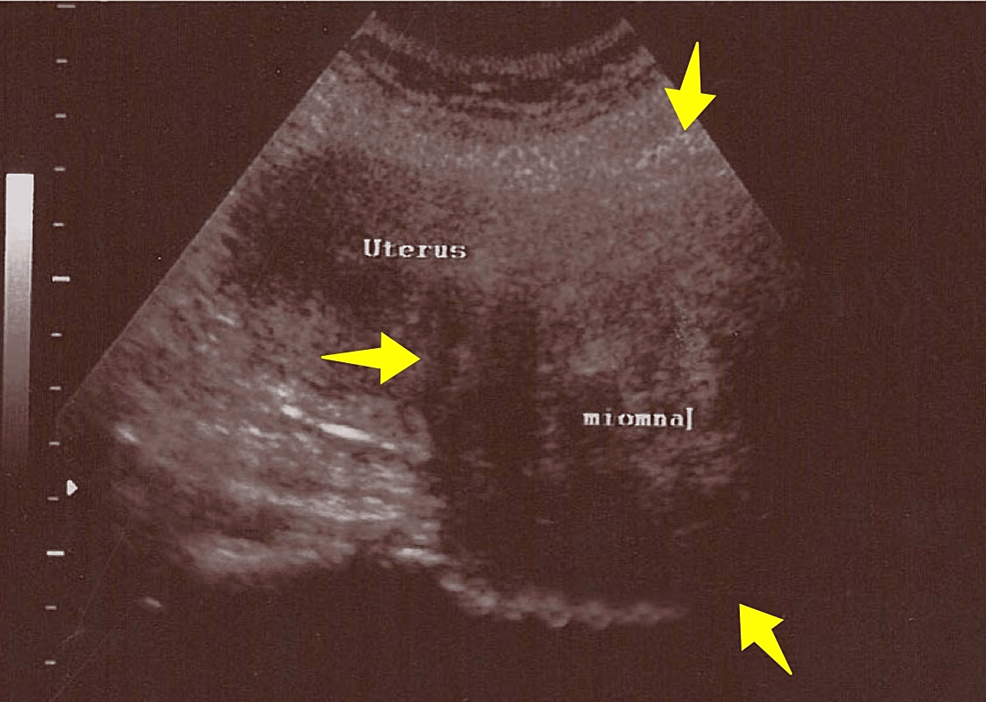

Ruptured ectopic molar pregnancy and ruptured uterine fibroid: a challenging rare diagnosis

Source : https://casereports.bmj.com/content/16/1/e251045.full

Although rare and unusual occurrences, a ruptured ectopic molar pregnancy (MP) and a ruptured uterine fibroid can lead to significant maternal morbidity and mortality. We present a unique case of...

Discussion: This is the first reported case of concurrent ruptured ectopic MP and ruptured uterine fibroid.